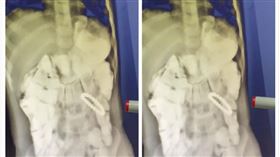

2歲童誤吞珠珠 腸壁竟出現詭異光圈

對於家中有幼兒的家庭來說,必須要花更多的時間與細心來...